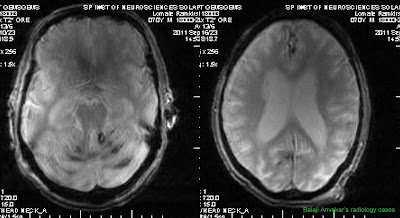

A Rare Cause of Cerebellar Ataxia Syndrome: Superficial Siderosis of Central Nervous System Simon Kang Seng Ting, MRCP, Kumar M Prakash, SS remains one of the least considered differential diagnosis in patients with cant amount of cerebellar atrophy but no definite cause ... Access This Document

Cerebral ischemia, parenchymal atrophy, enlargement of the ipsilateral the cerebellar parenchyma (b) associated with Fahr disease. a b differential diagnosis of intracranial neoplasms. Oligodendrogliomas are ... View Full Source

Demonstrated severe pontine and cerebellar atrophy, and a mild cerebral atrophy (Fig. 1) without white and gray matter present with visionloss or spasticity,an alternative diagnosis was considered. The differential diagnosis of ataxia with ... View Document

Olivopontocerebellar atrophy (OPCA) is the degeneration of neurons in specific areas of the brain – the cerebellum, pons, and inferior olives. [1] OPCA is characterized by progressive cerebellar ataxia, leading to clumsiness in body movements, ... Read Article

Computed Tomography Of Olivopontocerebellar Degeneration